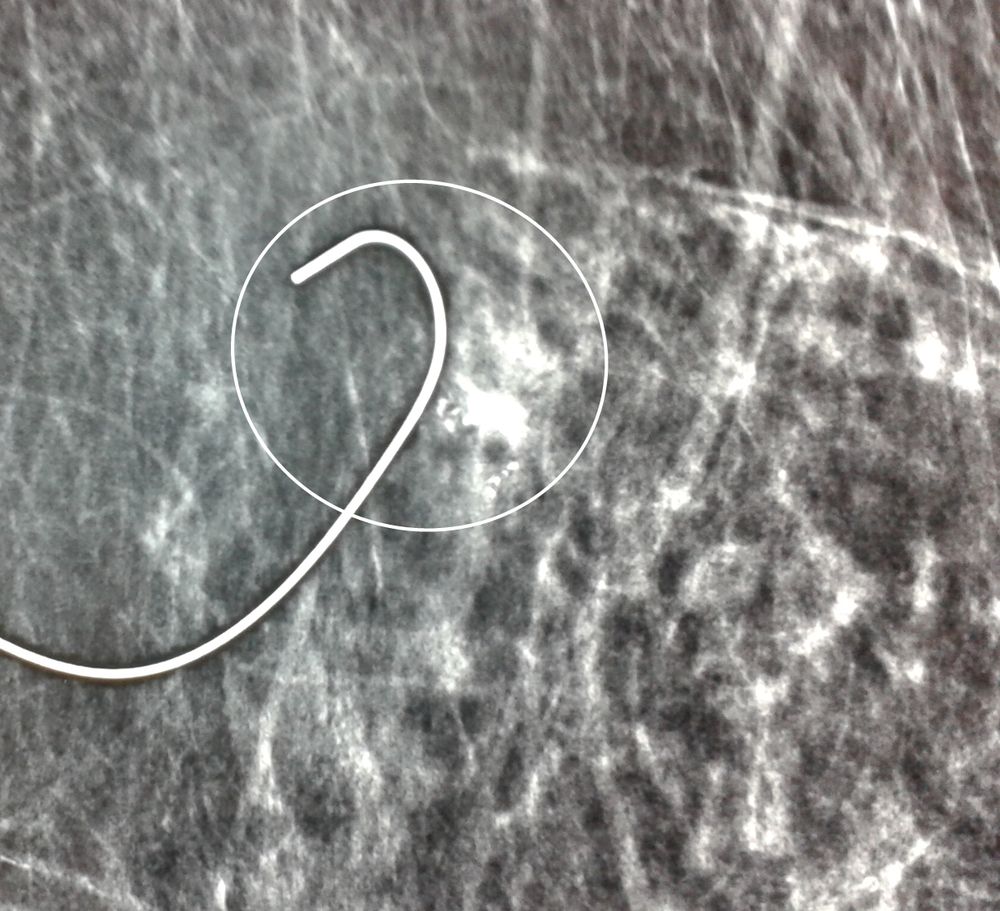

Σε περίπτωση που απαιτείται η χειρουργική αφαίρεση ενός ευρήματος που δε ψηλαφάται από το χειρουργό, τότε γίνεται η τοποθέτηση αγκίστρου σήμανσης (hook) λίγο πριν το χειρουργείο. Το άγκιστρο έχει σκοπό να καθοδηγήσει το χειρουργό για την αφαίρεση του σωστού τμήματος του μαστού, ώστε να αφαιρεθεί με ασφάλεια η ύποπτη βλάβη χωρίς να επηρεασθεί η αισθητική εικόνα του μαστού, πράγμα πολύ σπουδαίο ειδικά σε νέες γυναίκες και σε γυναίκες με μικρό μαστό.